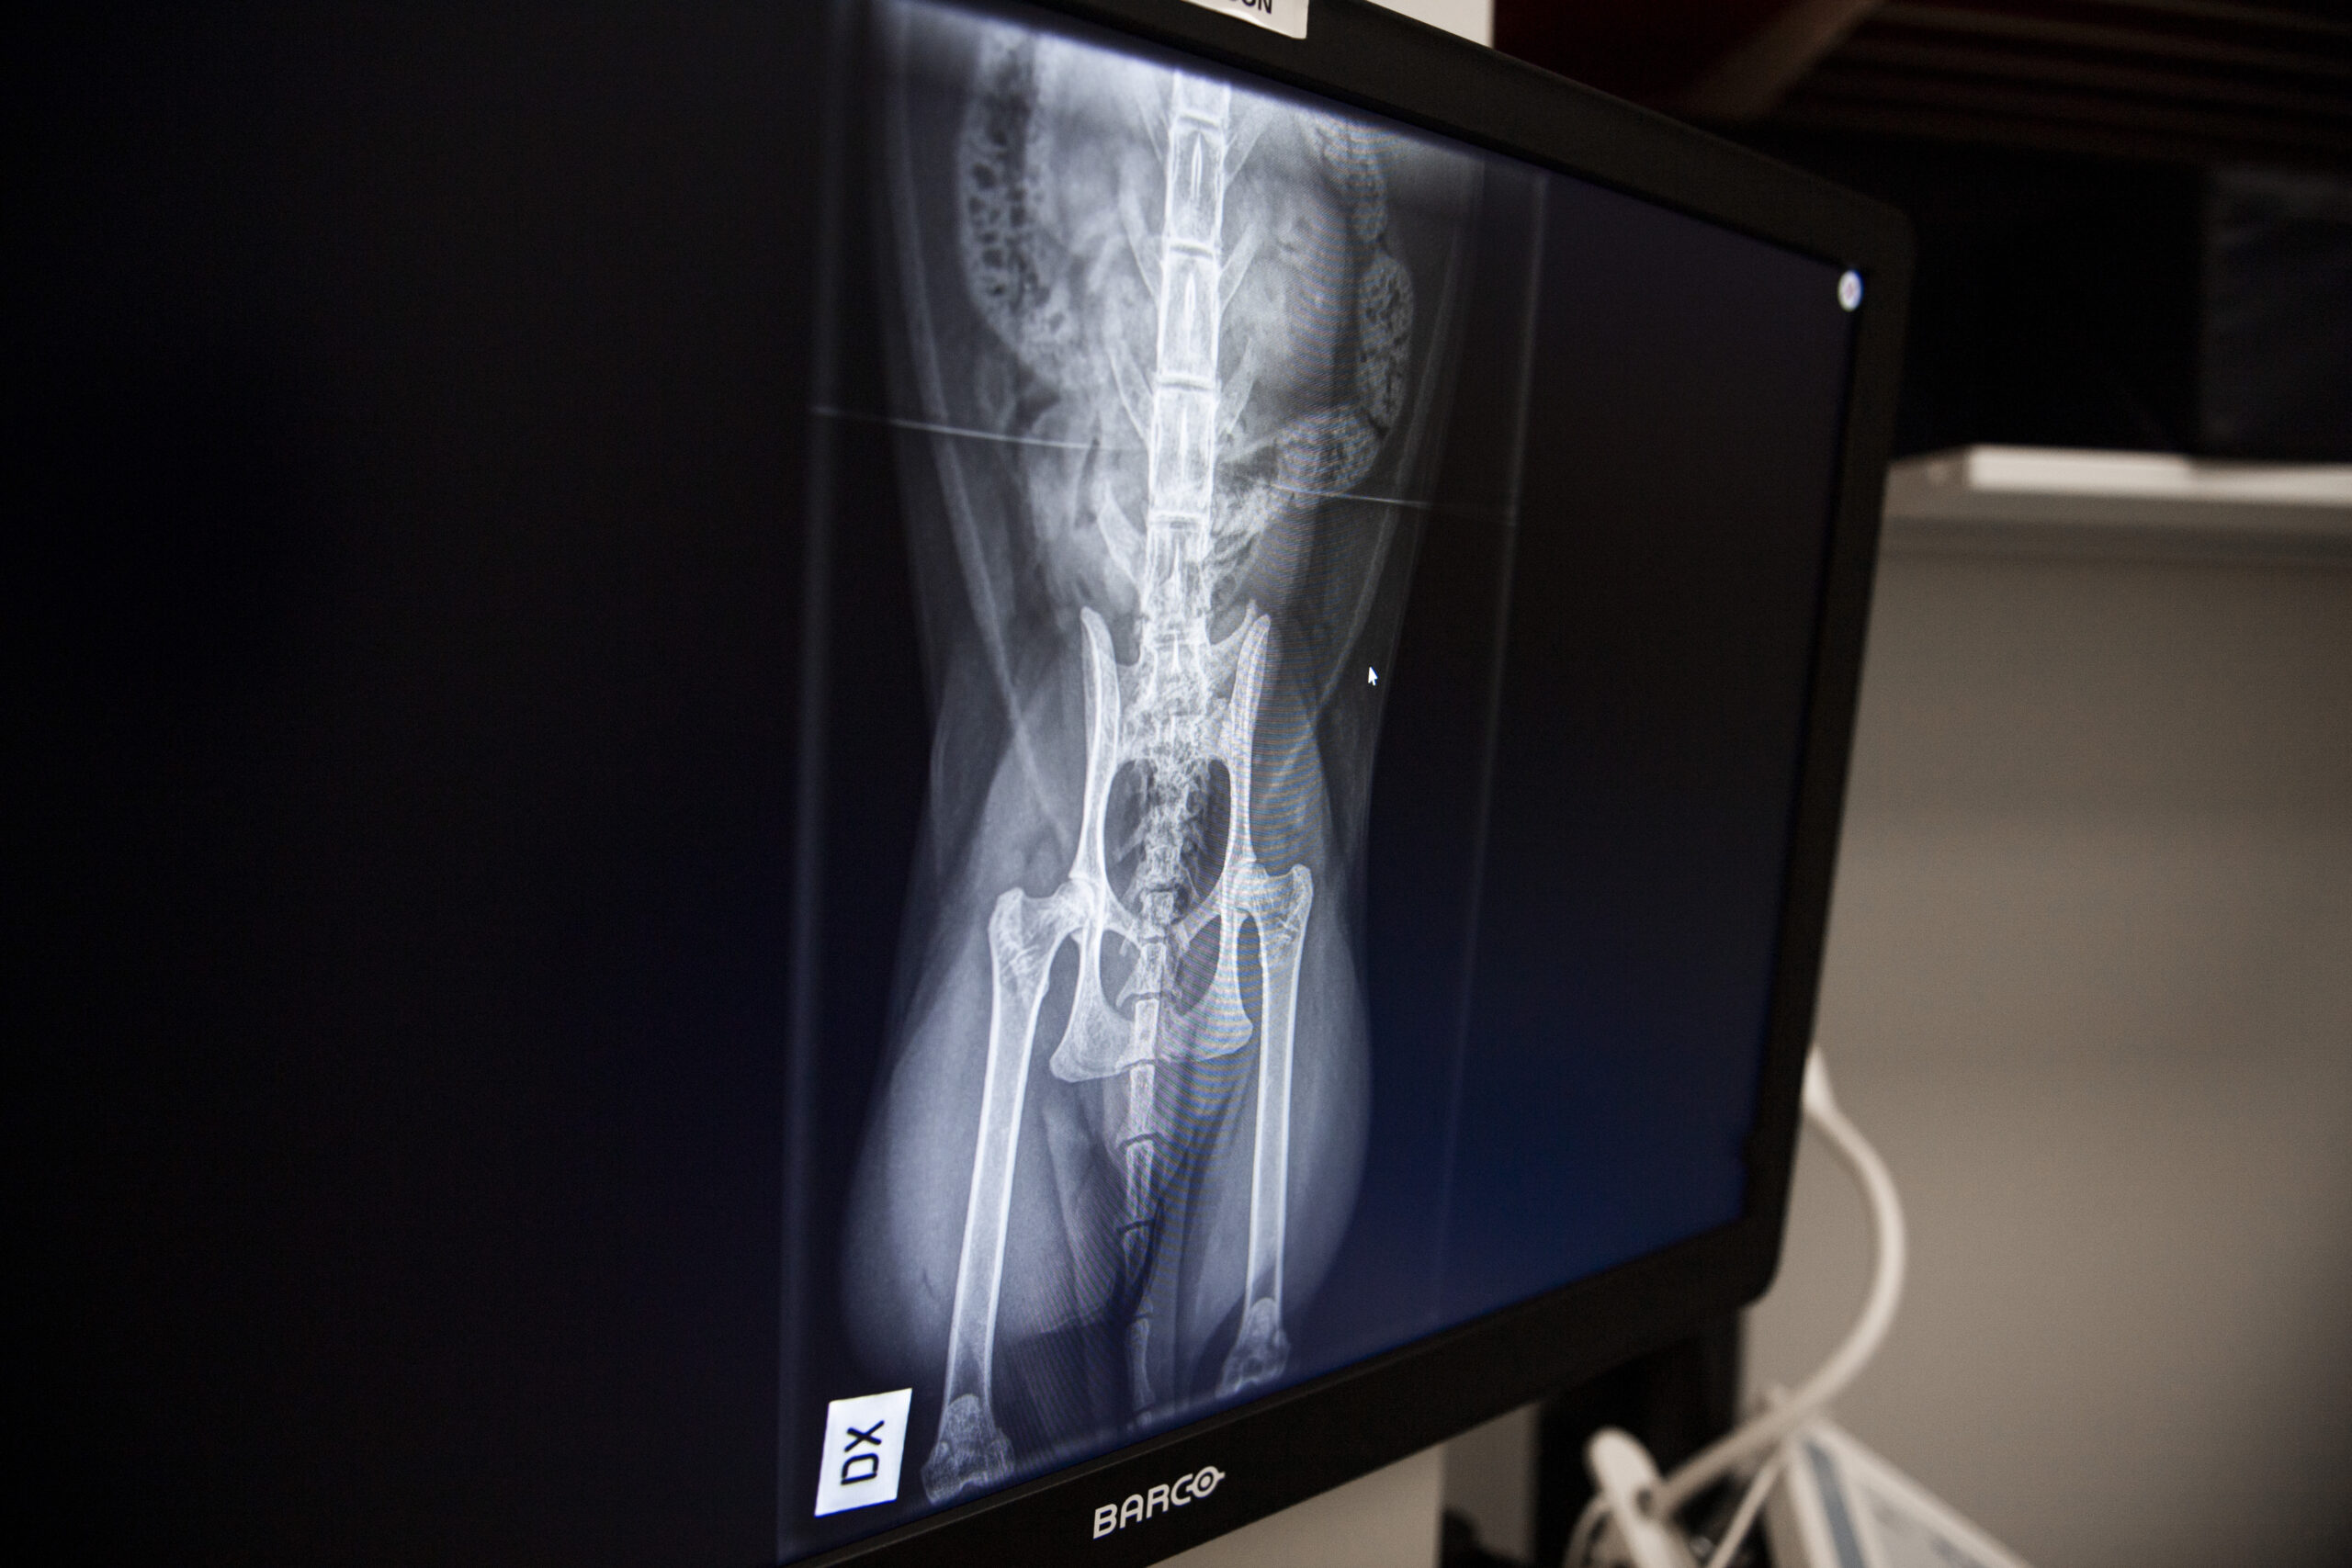

Jos huomaat koirallasi lonkkavian oireita, on tärkeää hakeutua eläinlääkärin vastaanotolle mahdollisimman pian. Eläinlääkäri voi tehdä tarvittavat tutkimukset, kuten röntgenkuvaukset, ja antaa tarkempia hoitosuosituksia.